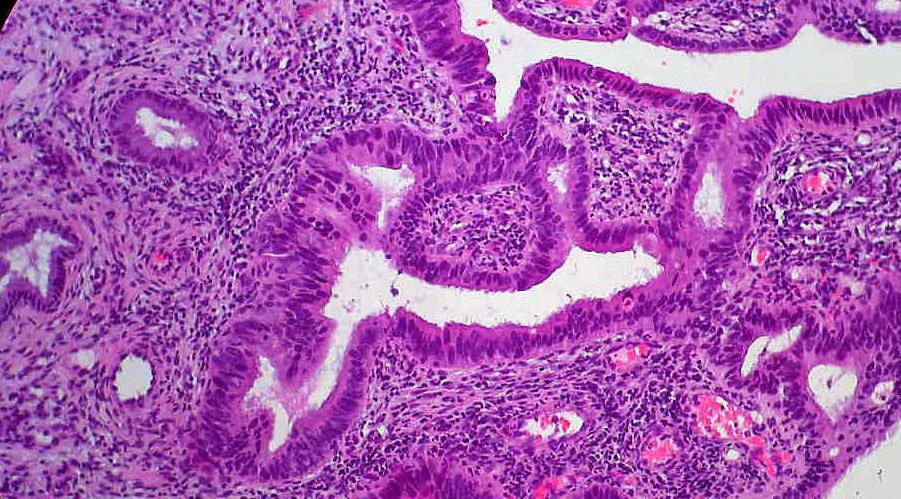

• CIBERONC

I Reunión del Programa de Tumores del Tracto Digestivo

18/10/2017